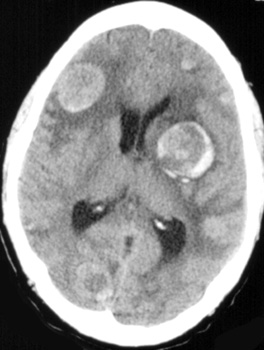

Multiple enhancing masses located at the grey-white junction zones.